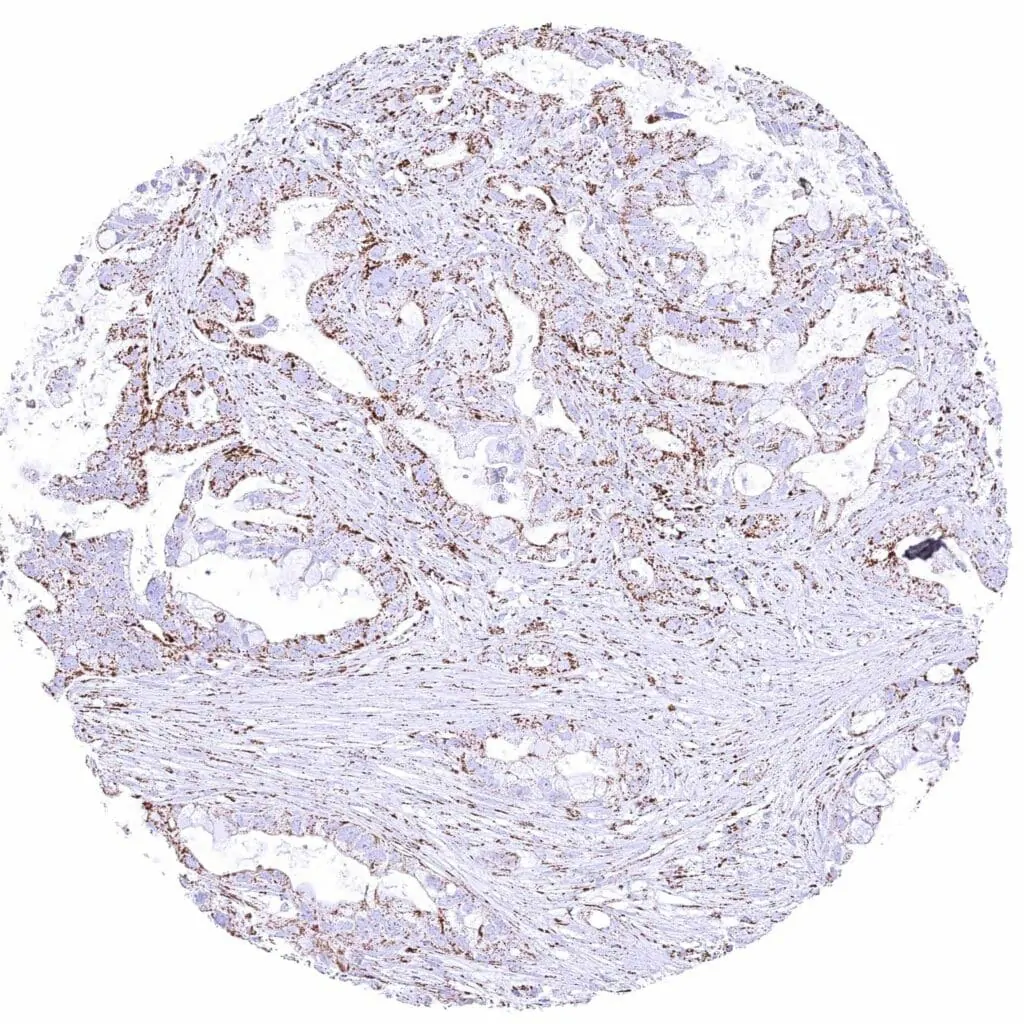

Pancreas – Ductal adenocarcinoma with weak cytoplasmic ATP5J immunostaining of tumor cells.